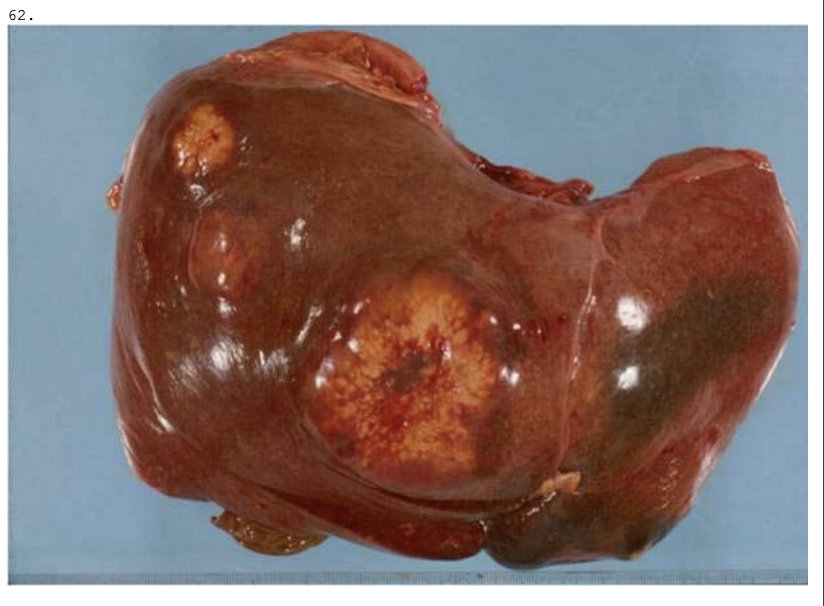

En 55-årig mand findes død i eget hjem. Ved obduktion ses forandringer i leveren som vist på billedet. Hvilket er følgende af udsagn er korrekt?

a. Der er tale om en atrofisk vækstforstyrrelse.

b. Tilstanden er ikke relateret til alkohol.

c. Makroskopisk beskrives leveren som forstørret og blød.

d. Tilstanden er irreversibel.

e. Mikroskopisk ses fibrøse strøg og regenererende hepatocytter.

*c. Makroskopisk beskrives leveren som forstørret og blød.